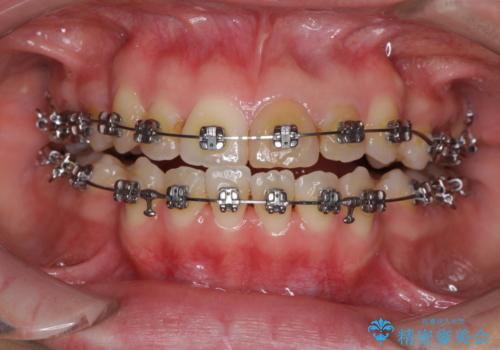

- 矯正装置

- メタルブラケット

- 上の八重歯を気にして来院された患者様です。

受け口傾向にあるため、上顎前歯の叢生解消とともに下顎前歯を後方へ移動させることを目的とし、上下左右の第一小臼歯4歯を抜歯することとしました。